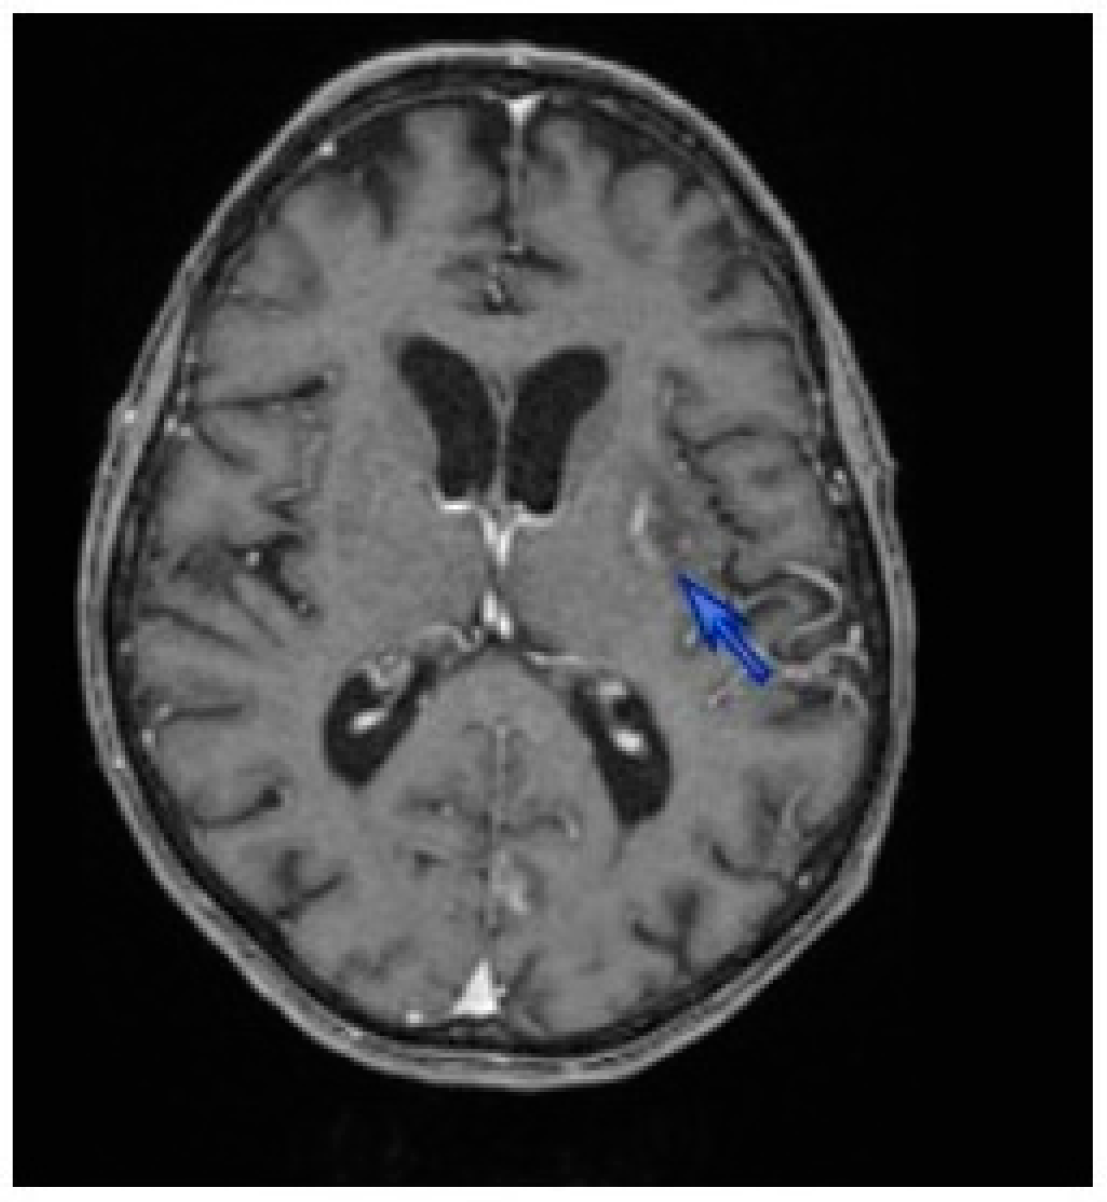

2. Case Description